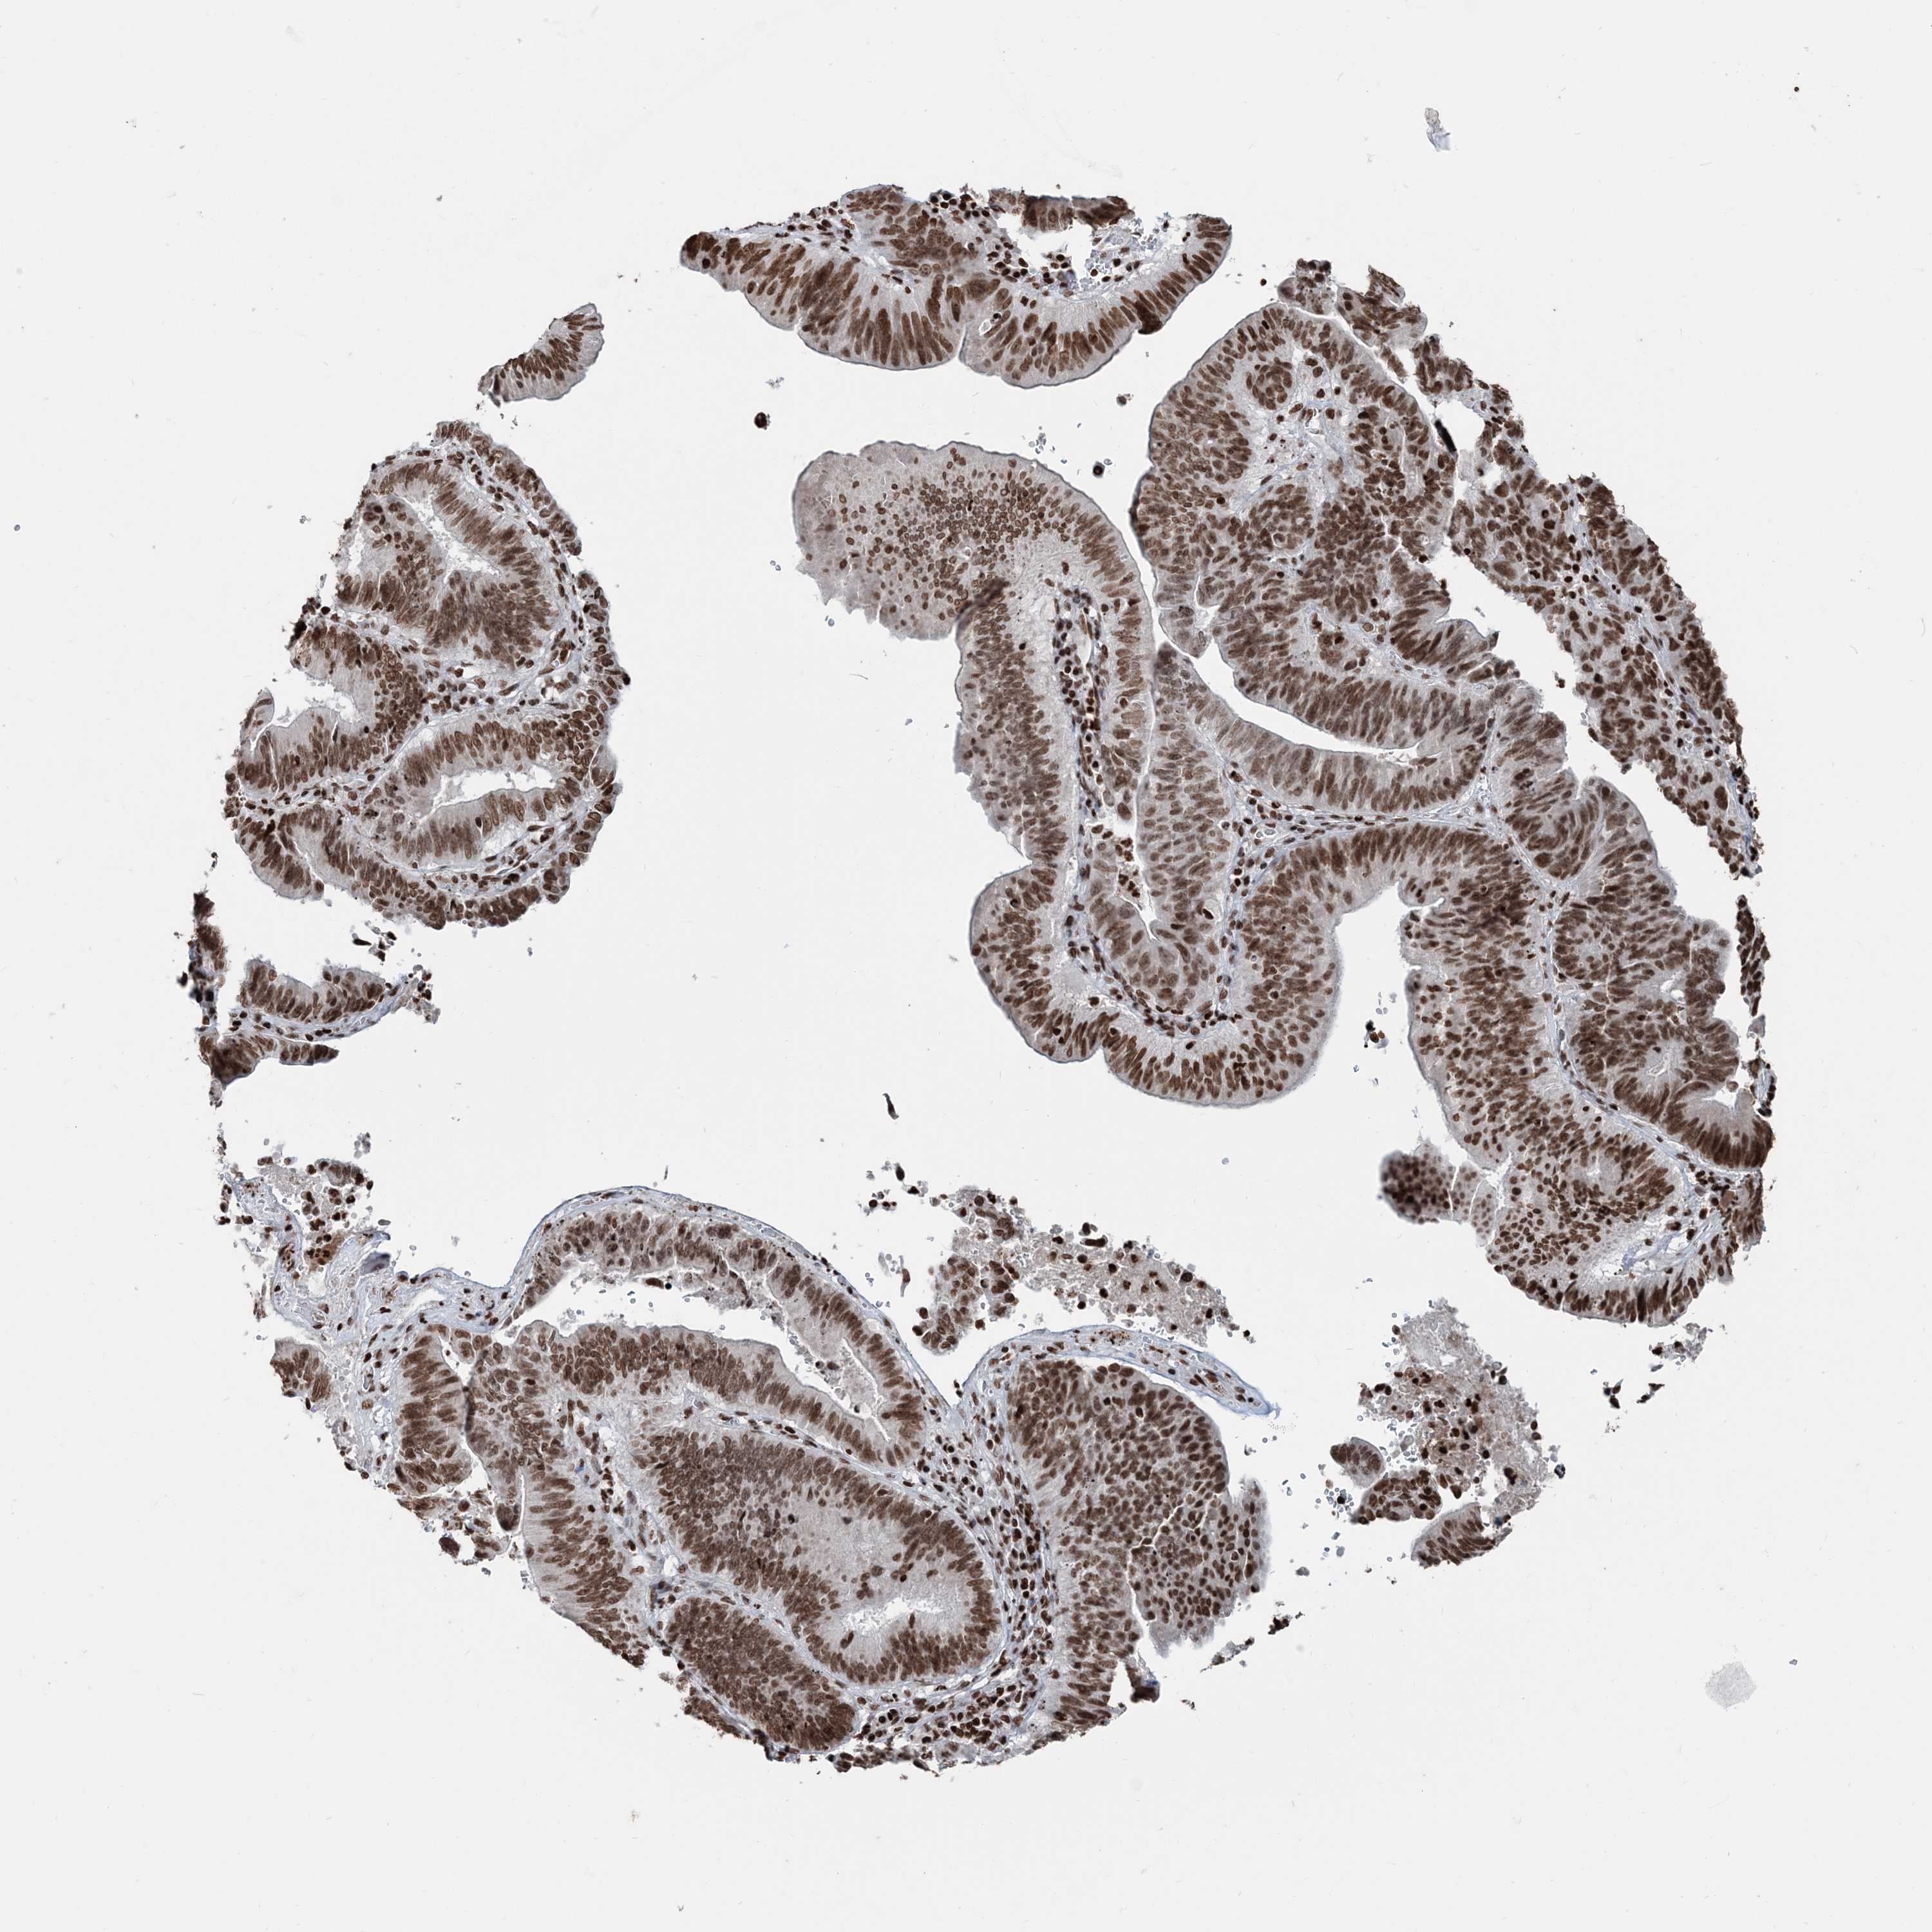

PANCREATIC CANCER - Protein expressioni

A mouse-over function shows sample information and annotation data. Click on an image to view it in a full screen mode. Samples can be filtered based on level of antibody staining by selecting one or several of the following categories: high, medium, low and not detected. The assay and annotation is described here.

Note that samples used for immunohistochemistry by the Human Protein Atlas do not correspond to samples in the TCGA dataset.

Antibody stainingi

Antibody staining in the annotated cell types in the current human tissue is reported as not detected, low, medium, or high, based on conventional immunohistochemistry profiling in selected tissues. This score is based on the combination of the staining intensity and fraction of stained cells.

Each image is clickable and will lead to virtual microscopy that enables deeper exploration of all samples and also displays staining intensity scores, fraction scores and subcellular localization as well as patient and tissue information for each sample.

Antibody HPA042570

Antibody CAB037166

Antibody CAB037187

Antibody CAB037221

Staining

High

Medium

Low

Not detected

Intensity

Strong

Moderate

Weak

Negative

Quantity

>75%

75%-25%

<25%

None

Location

Nuclear

Cytoplasmic/membranous

Cytoplasmic/membranous,nuclear

Adenocarcinoma, NOS